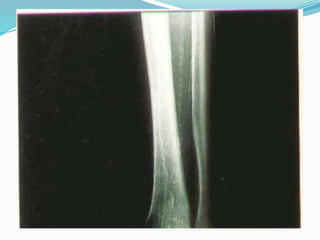

Case 2